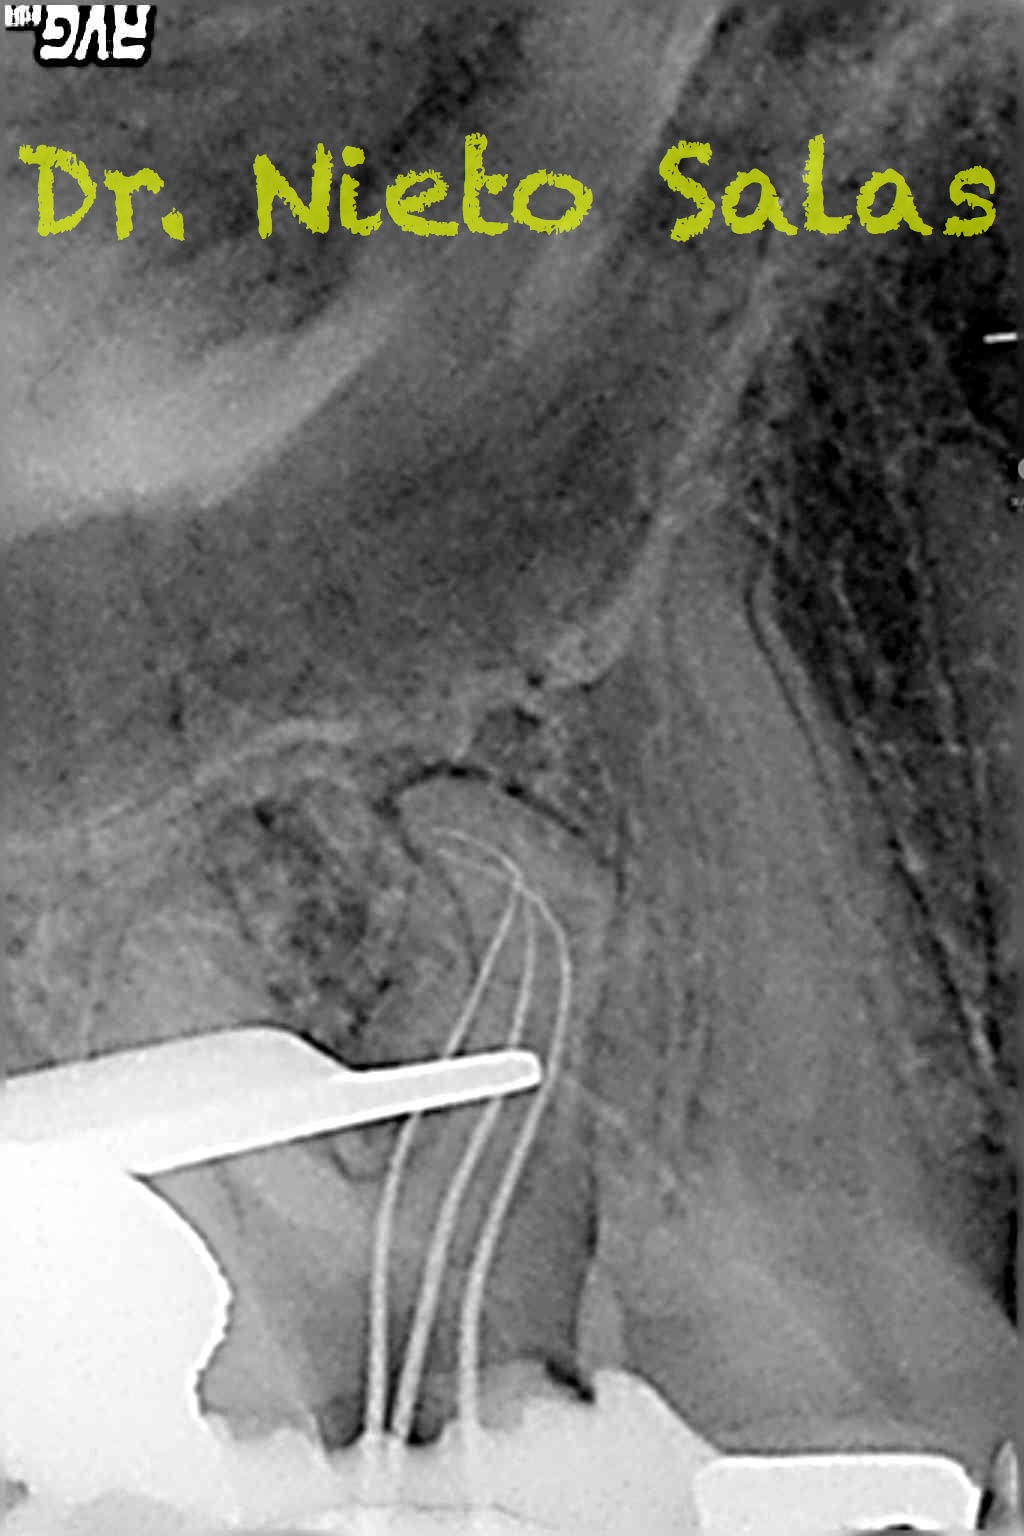

Una vez desobturados los conductos, empezamos a hacer una endodoncia convencional.

A este caso le tengo especial cariño por ser el primero que hice;